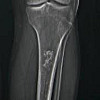

КТ трубчатых костей ребенку

КТ трубчатых костей ребенка включает послойное рентгеновское сканирование бедренной кости и плечевой кости, предплечья и костей голеней, а также мелких костей фаланг рук и ног. Компьютерная томография позволяет визуализировать кортикальный и губчатый слои, полость костного мозга и мягкие ткани конечностей. КТ трубчатых костей ребенка проводится в детской травматологии и ортопедии для диагностики переломов, воспалительных процессов в костях (туберкулез, остеомиелит), опухолей, исходов и осложнений патологических процессов. Обычно КТ трубчатых костей назначают после рентгенологического исследования для уточнения диагноза.